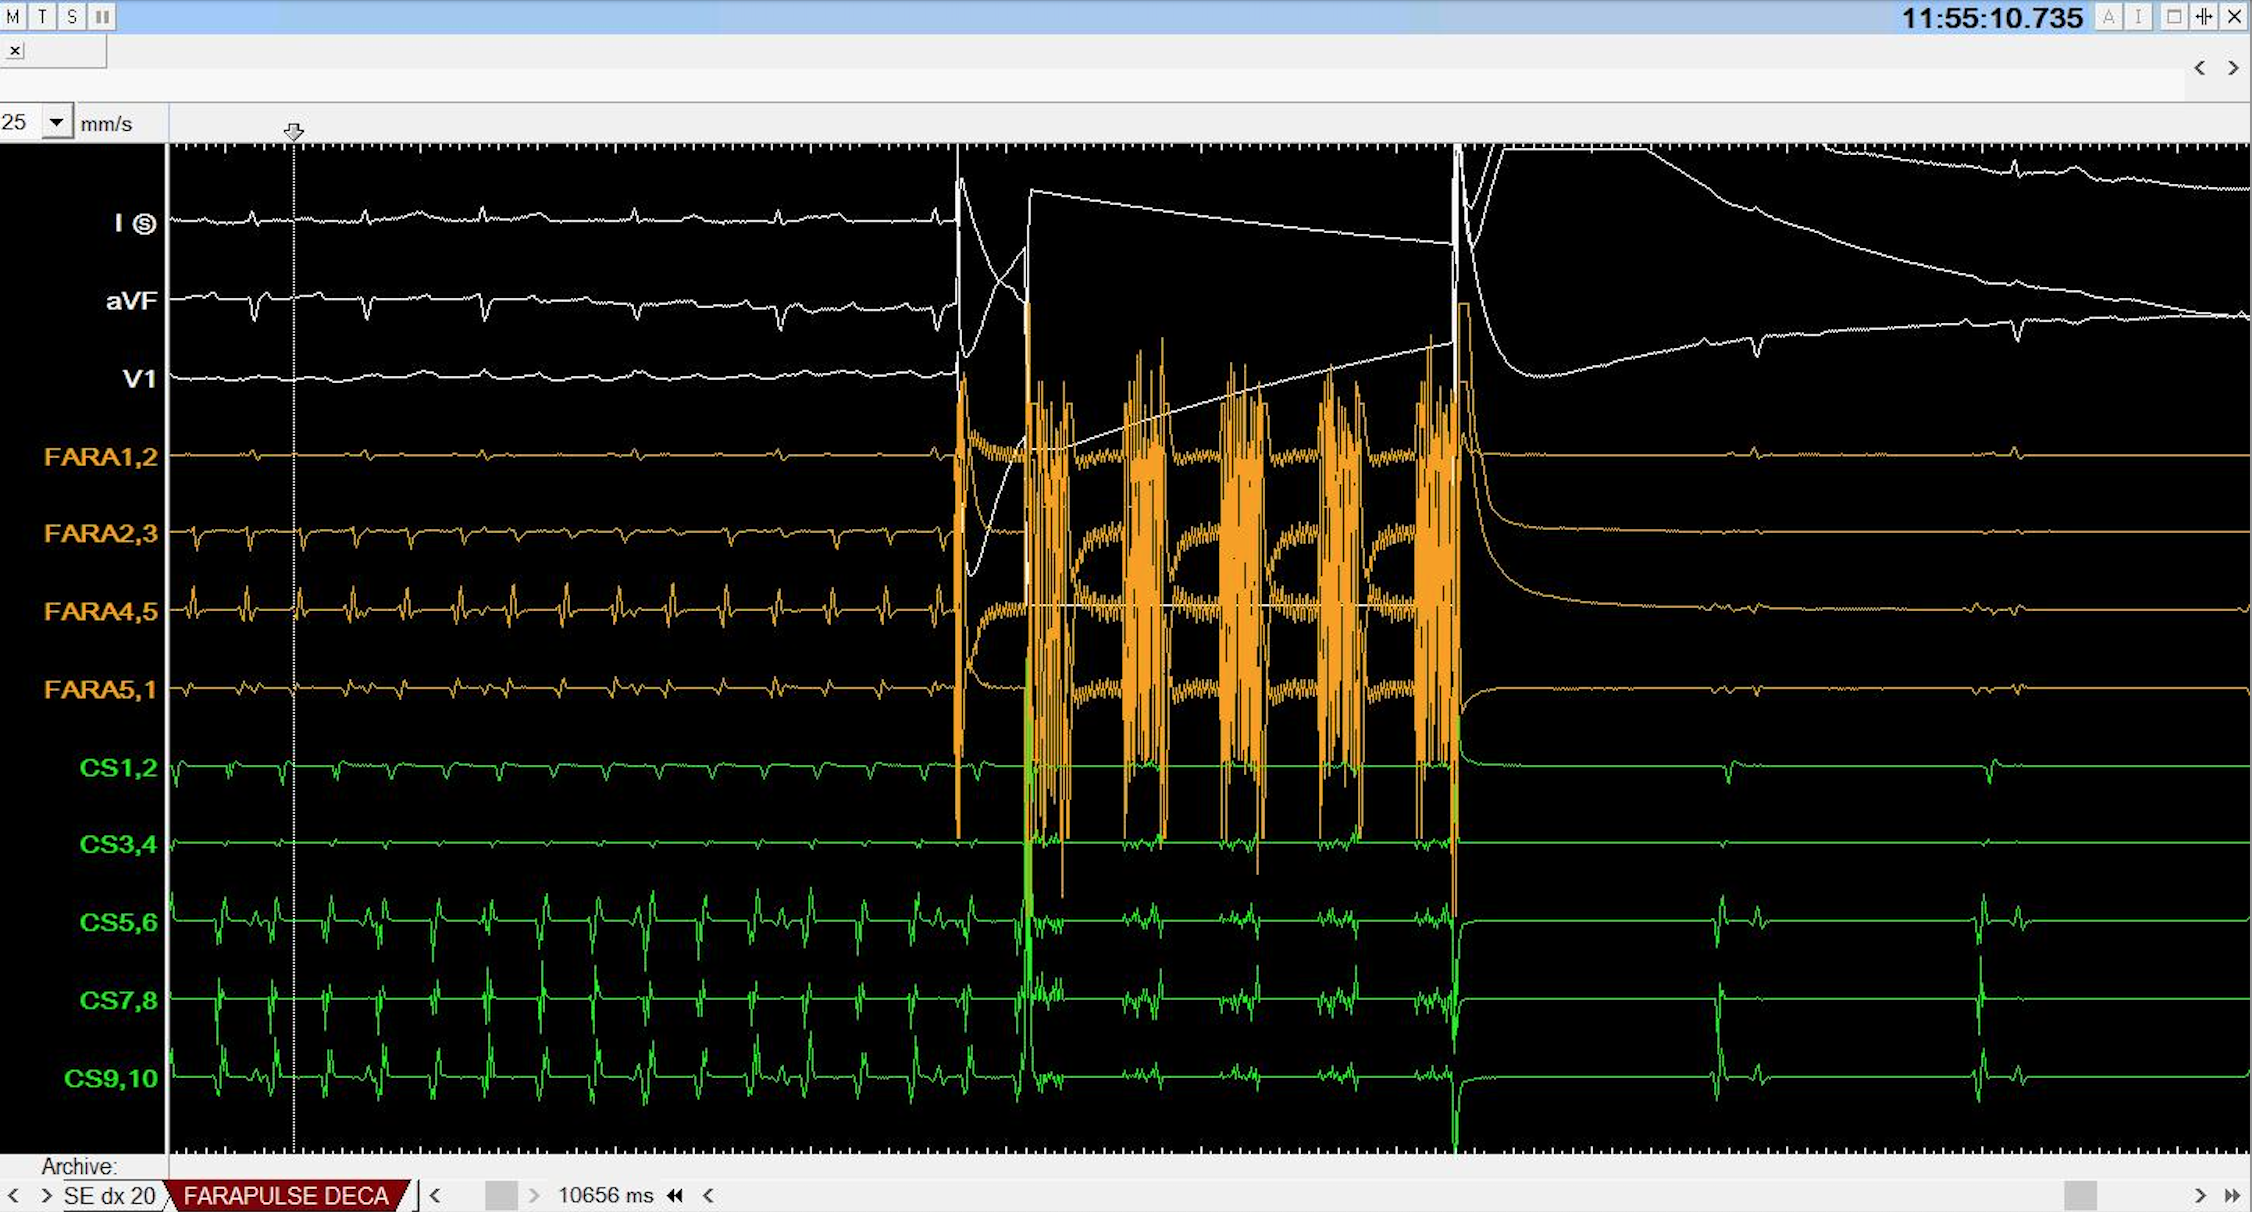

Introduccion La ablación por campo pulsado (PFA, por sus siglas en inglés) es...

INTRODUCCIÓN La ablación de fibrilación auricular (AbFA) con campo pulsado (...